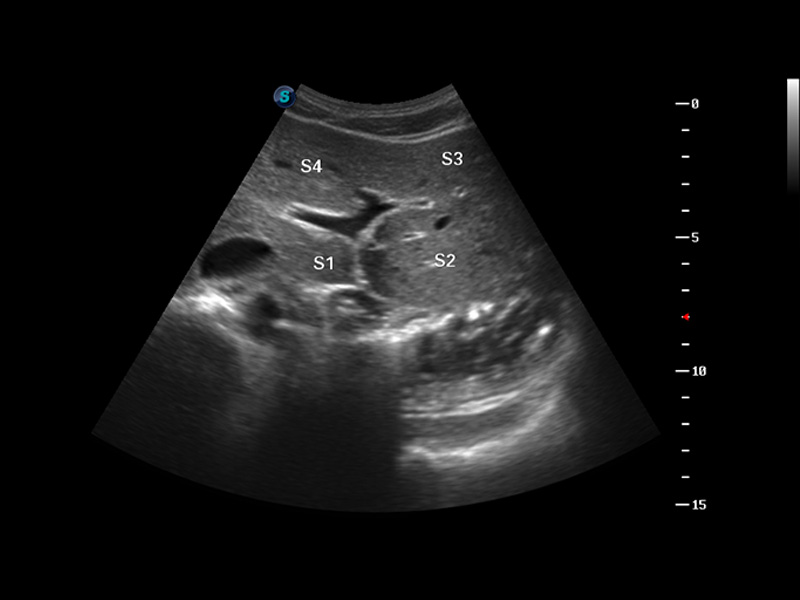

S8 EXP便携式彩色多普勒超声诊断仪是环球UG官网研发的高端全身应用型便携彩超。高通道的VIS平台融合可视化(Visual)、智能化(Intelligent)和人性化(Smart)的特点,配以环球UG官网自主研发生产的探头大家族,使您能够快速、准确的获得病人信息,提高工作效率的同时减轻疲劳。

成像技术

μ-Scan微米成像

谐波成像

空间复合成像

3D/4D成像